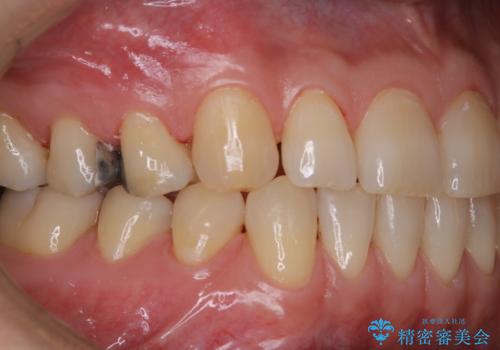

タバコとコーヒーによる頑固な着色落とし

- 毎日の喫煙とコーヒーを飲むことにより、ひどく着色がついてしまったとのことです。PMTC60分コースを行いました。

PMTC(保険外治療)は、毎日の歯磨きで落としきれない汚れや、コーヒ、紅茶・タバコのヤニなどの着色も除去します。目には見えない歯と歯の間・歯肉の境目などに残っているプラーク(歯垢)もしっかり取り除きます。PMTCでは専門的な機械や材料を使用して、徹底的に汚れを除去するため、虫歯・歯周病・口臭予防などにつながります。

また、仕上げのトリートメントでは歯の表面の凸凹にミネラルを補給して、ツルツルの表面に仕上げます。定期的にPMTCを行うことにより、歯質の強化になり着色がつきにくい状態になります。